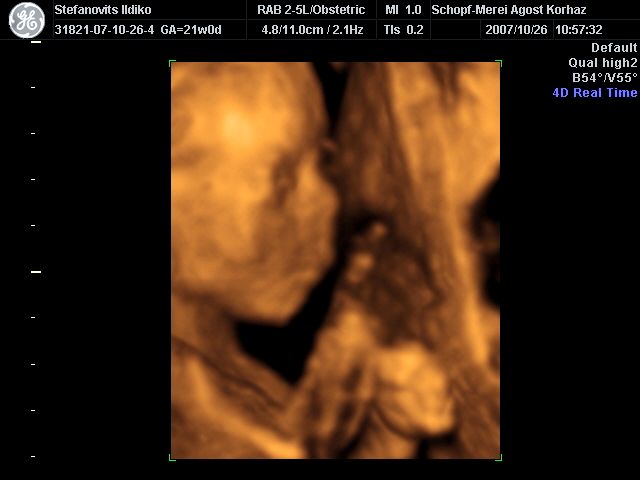

4D Ultrahang - 21+1 (07/10/26, Bp.)

4D - 11